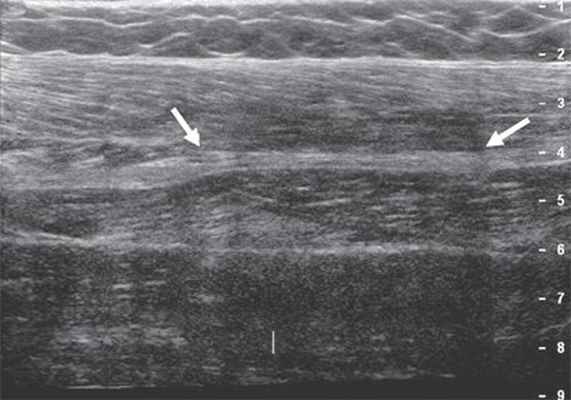

Ультразвуковое исследование периферических нервов целесообразно начинать с поперечной проекции в точке, где нервный ствол легче всего идентифицировать, смещаясь затем в проксимальном и дистальном направлениях, оценивая структуру нерва на протяжении 3.

Изображение нерва имеет ряд характерных признаков. В поперечной проекции он выглядит как овальное или округлое образование с четким гиперэхогенным контуром и внутренней гетерогенной упорядоченной структурой ("соль - перец", "медовые соты") [4, 6, 7]. В продольной проекции нерв лоцируется в виде линейной структуры с четким эхогенным контуром, в составе которой правильно чередуются гипо- и гиперэхогенные полосы - "электрический кабель" [7]. Толщина периферических нервов вариабельна и составляет от 1 мм для пальцевых нервов до 8 мм для седалищного нерва.

Большеберцовый нерв по своему направлению является продолжением седалищного нерва. В подколенной ямке нерв располагается над подколенными веной и артерией и несколько кнаружи от них (рис. 6).

Рис. 6. Сонограммы большеберцового нерва в подколенной ямке (стрелки). Визуализируется подколенный сосудистый пучок - вена (V) и артерия (A).